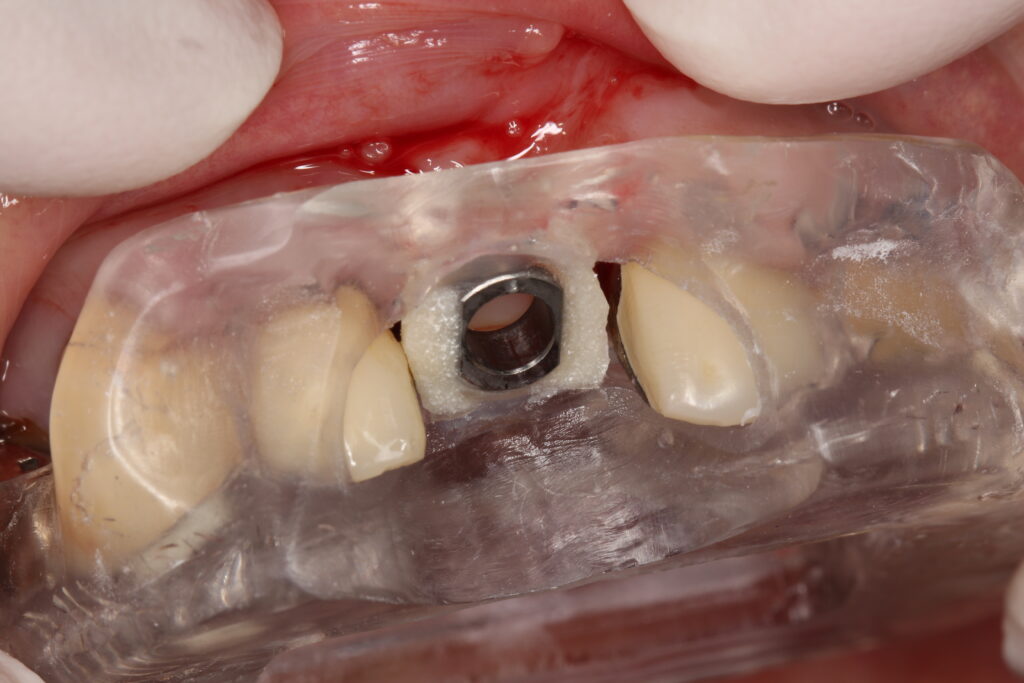

サージカルガイドシステムのインプラント治療とは、予めCT撮影なのでシュミレーションを行い設計されたガイドのマウスピースをはめて手術を行う技法です。

設計通りに正確な位置でインプラントを埋入でき、手術は低侵襲で術後の痛みも出にくいのがメリットですが一方、マウスピースを作製するコストがかかることや、技術を持った歯科医師が限られている事がデメリットにあげられます。

インプラントの埋入手術を行います。作成したガイドに従って、ガイド付きでインプラント手術を実行します。

また、CTでシュミレーションをして設計されたサージカルガイドを装着して手術を行うかも重要です。

サージカルガイドを装着してインプラント手術を行う事により、骨の深さや方向など、正確な位置にインプラント体を埋入する事が可能になります。